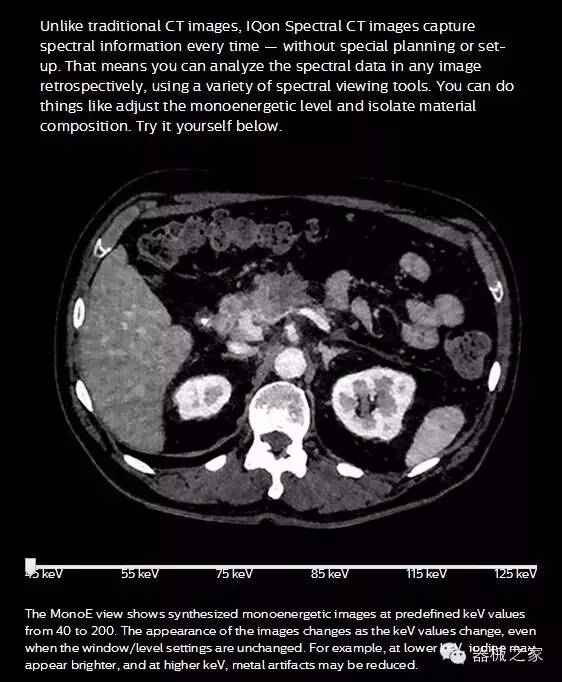

IQon光譜CT能夠按照需求提供光譜量化和工具,并能通過(guò)簡(jiǎn)單工作流程、在低劑量下對(duì)結(jié)構(gòu)進(jìn)行定性分析

IQon光譜CT -- 是業(yè)界首臺(tái)以探測(cè)器為成像基礎(chǔ)的光譜CT,它可以在單次常規(guī)掃描下獲得傳統(tǒng)解剖影像及光譜功能影像。不僅可以提供精準(zhǔn)的診斷信息,還可簡(jiǎn)化工作流程、在低劑量下完成定量與定性分析。